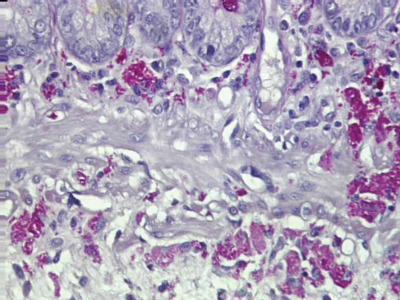

Debido a la rareza de la enfermedad y la complejidad de sus manifestaciones clínicas, es común que el diagnóstico se retrase o incluso se equivoque en ocasiones. A menudo, se requiere un conjunto de pruebas de laboratorio y biopsias de tejidos afectados para confirmar la presencia de Tropheryma whipplei en el organismo, lo que complica aún más su detección temprana y su manejo clínico. En consecuencia, la enfermedad de Whipple sigue siendo un enigma médico que plantea desafíos tanto para los profesionales de la salud como para los pacientes que la padecen.